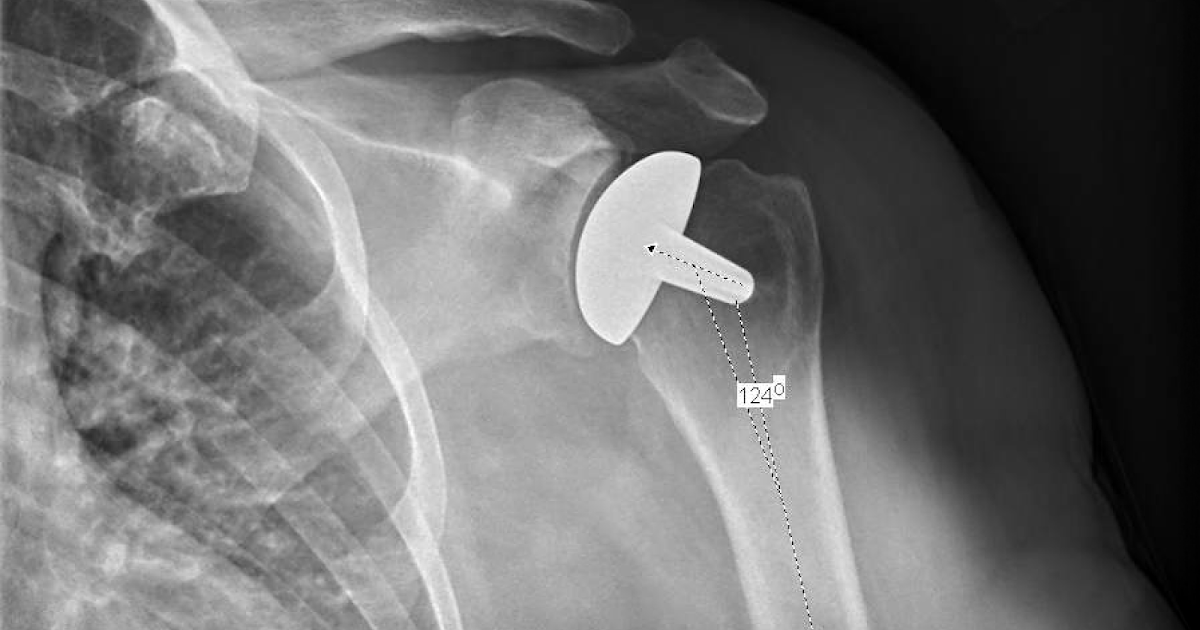

Clinical and radiologic following total shoulder arthroplasty